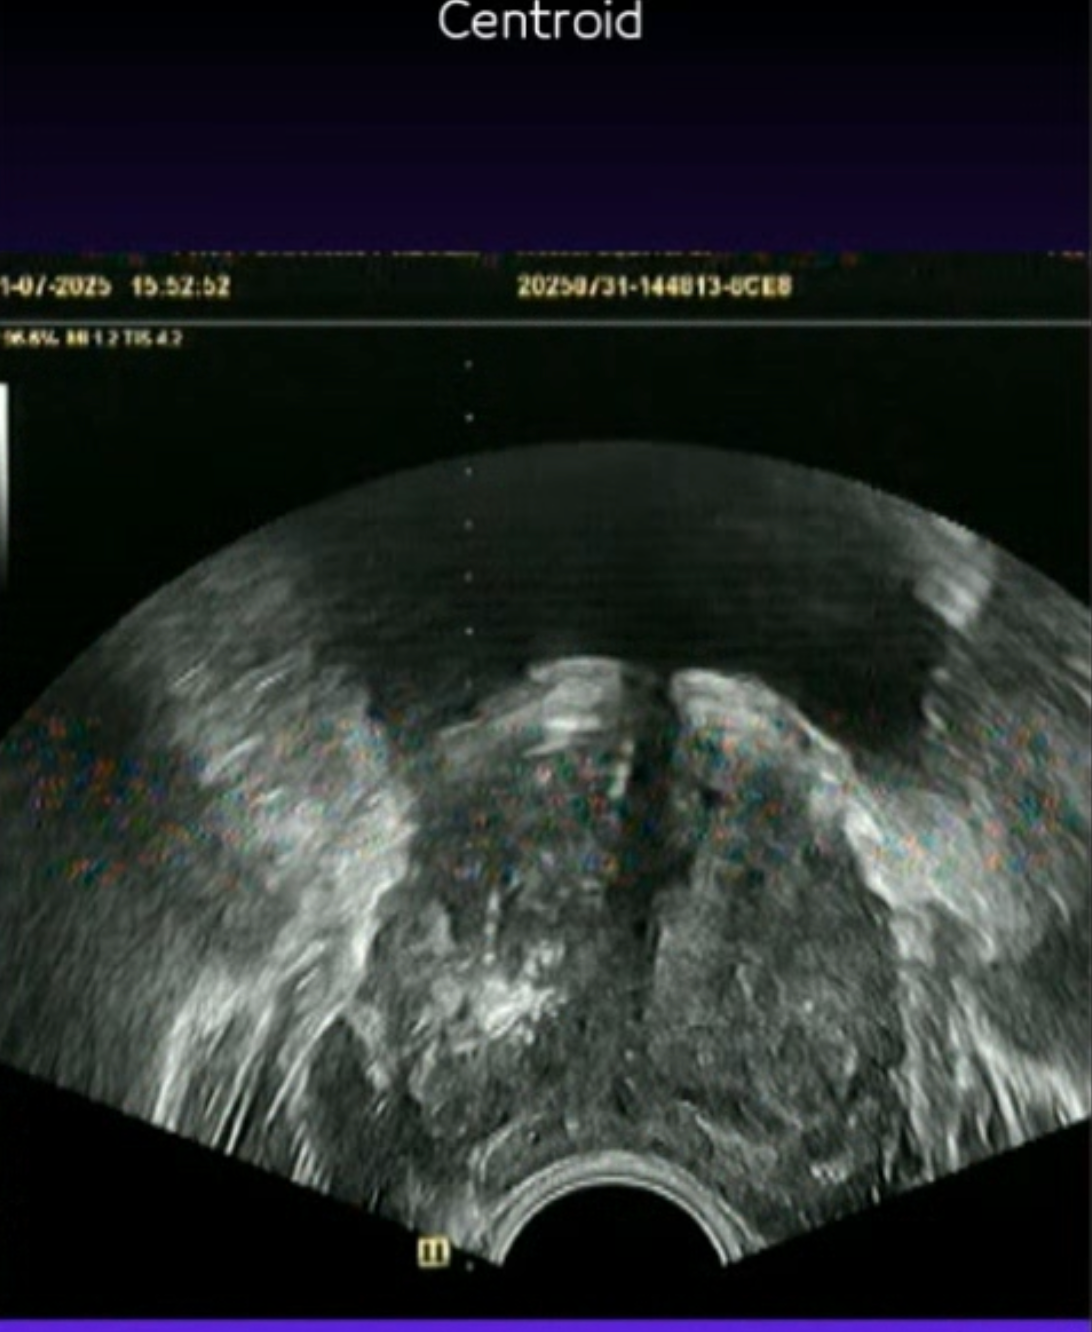

Prostat Füzyon Biyopsi

MR görüntüleri ile ultrason görüntülerinin birleştirilerek hedefe yönelik biyopsi yapılmasını sağlayan akıllı bir teknolojidir.

MR ve ultrason görüntüleri birleştirilir, **robotik sistemle** şüpheli hedeflerden hassas ve isabetli örnekler alınır.